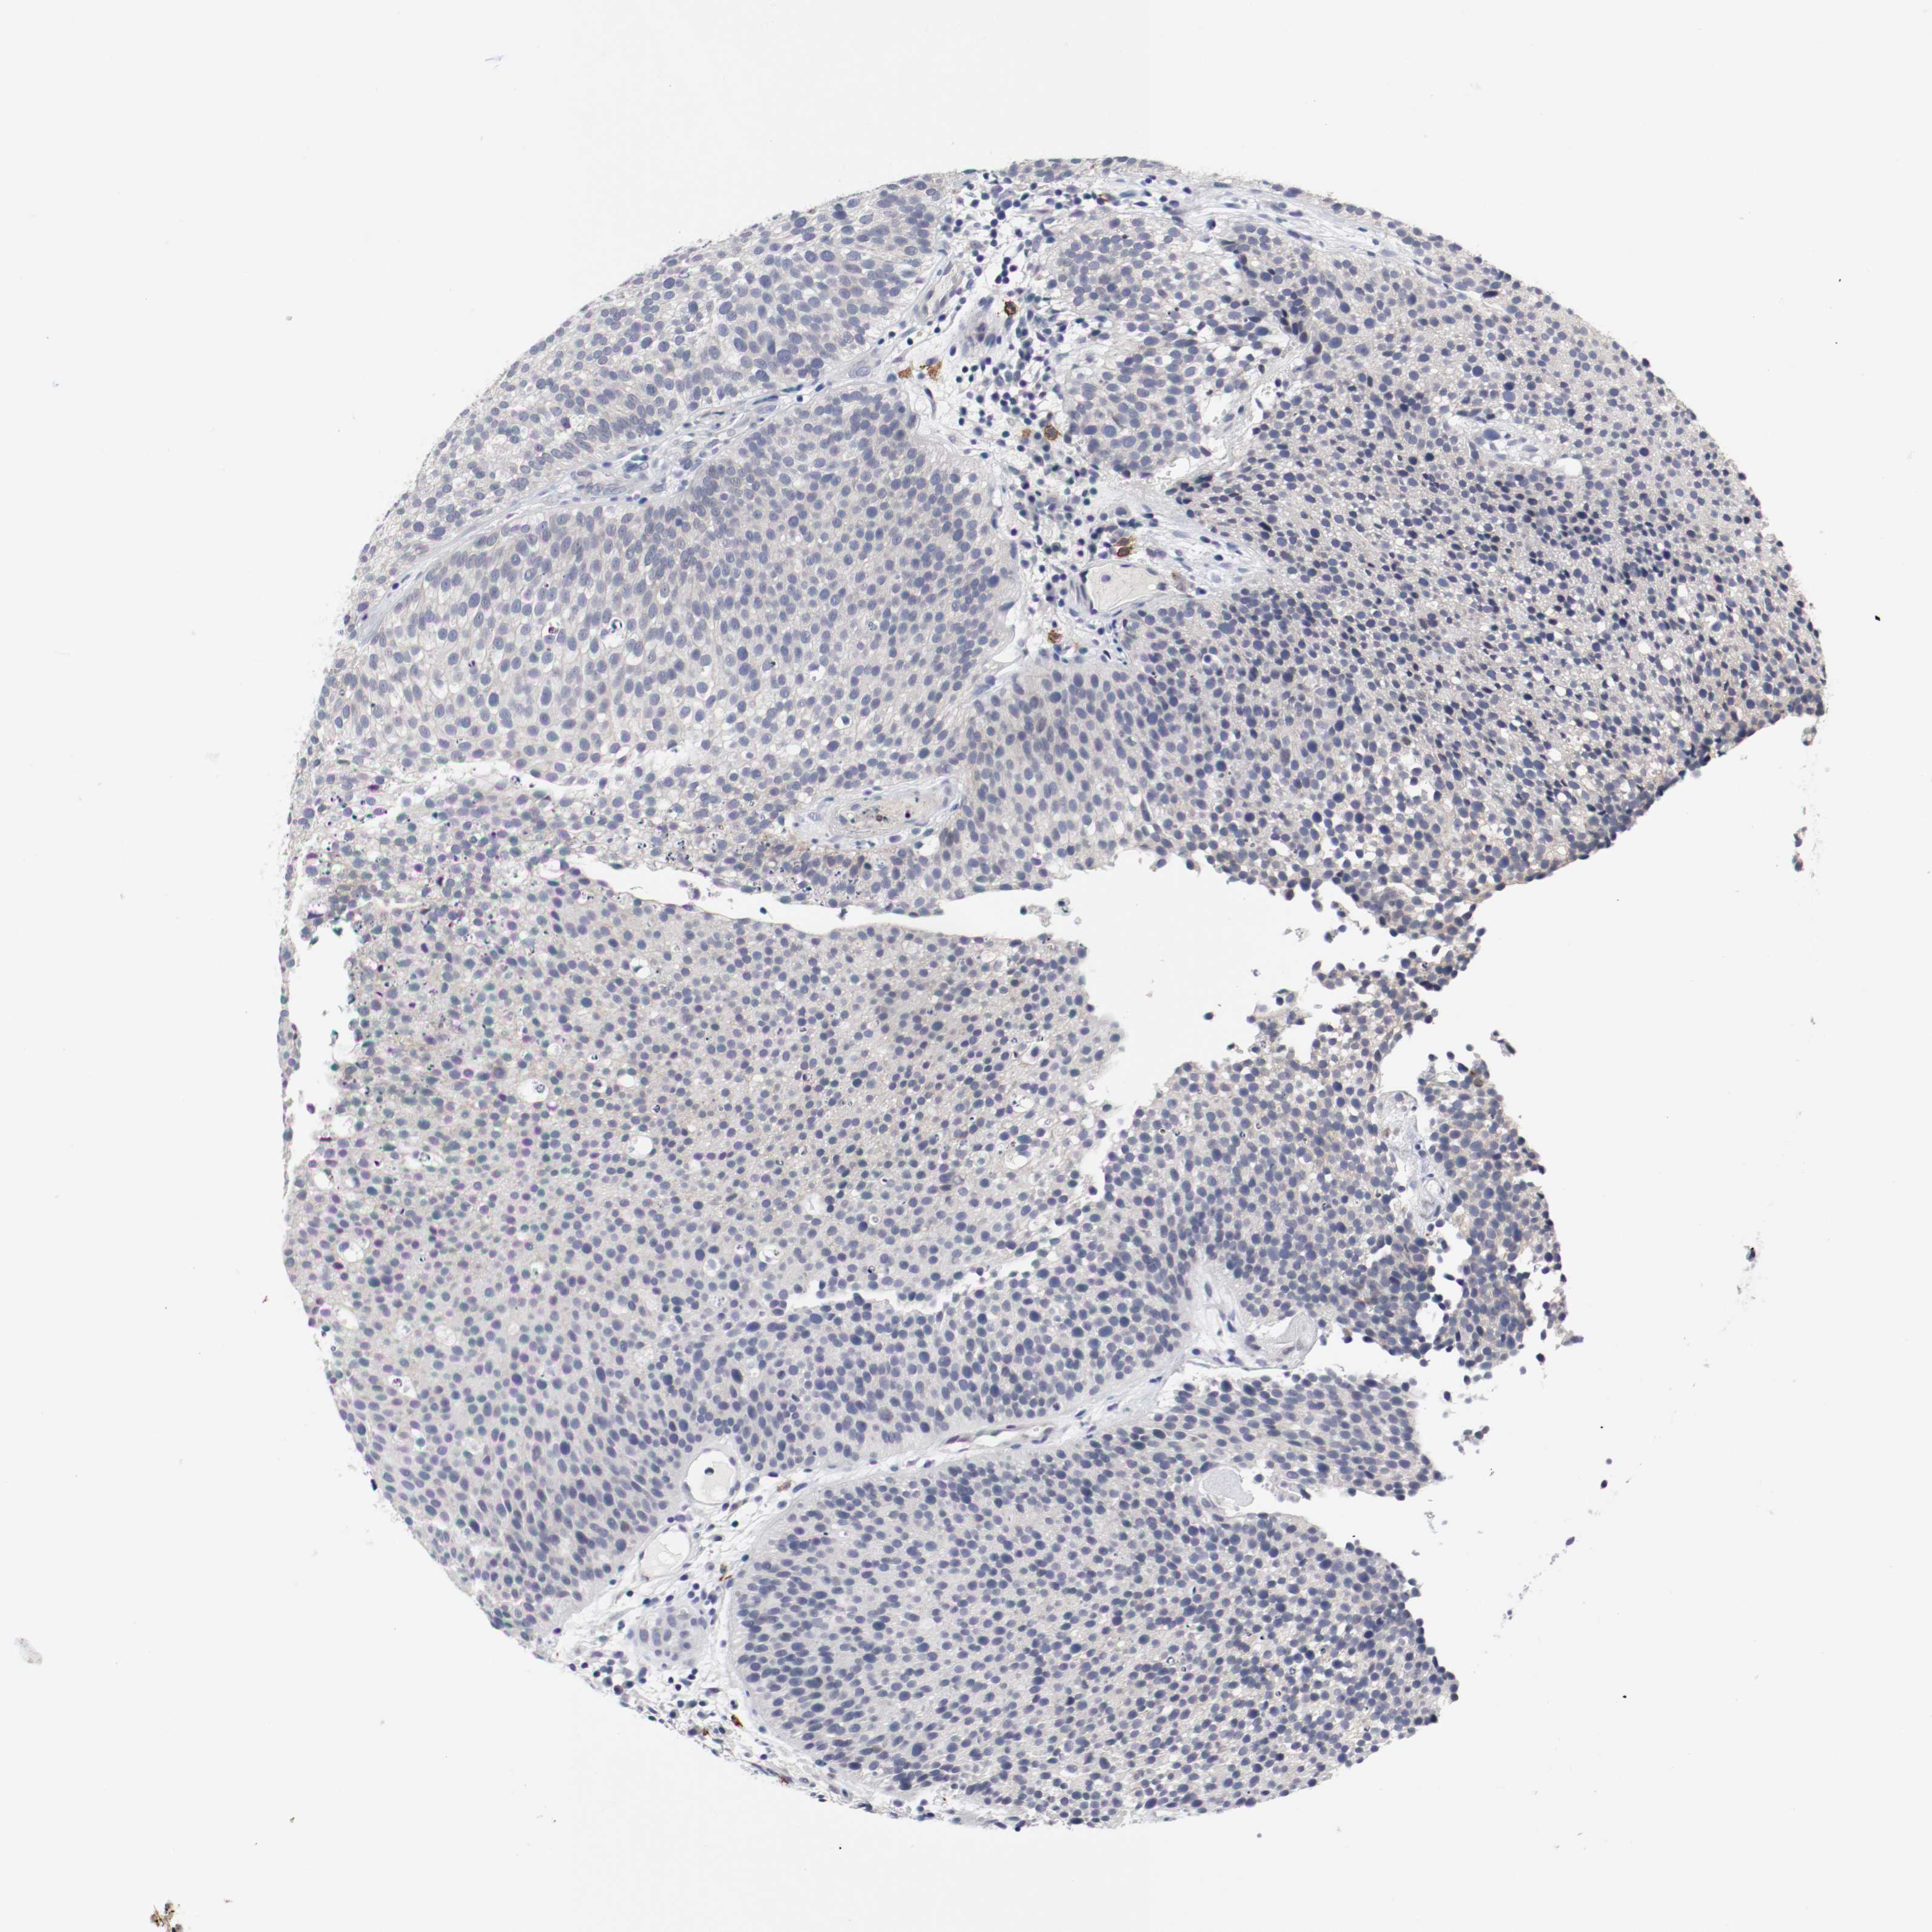

UROTHELIAL CANCER - Protein expressioni

A mouse-over function shows sample information and annotation data. Click on an image to view it in a full screen mode. Samples can be filtered based on level of antibody staining by selecting one or several of the following categories: high, medium, low and not detected. The assay and annotation is described here.

Note that samples used for immunohistochemistry by the Human Protein Atlas do not correspond to samples in the TCGA dataset.

Antibody stainingi

Antibody staining in the annotated cell types in the current human tissue is reported as not detected, low, medium, or high, based on conventional immunohistochemistry profiling in selected tissues. This score is based on the combination of the staining intensity and fraction of stained cells.

Each image is clickable and will lead to virtual microscopy that enables deeper exploration of all samples and also displays staining intensity scores, fraction scores and subcellular localization as well as patient and tissue information for each sample.

Antibody HPA004471

Antibody CAB003288

Antibody CAB068253

Antibody CAB072867

Staining

High

Medium

Low

Not detected

Intensity

Strong

Moderate

Weak

Negative

Quantity

>75%

75%-25%

<25%

None

Location

Nuclear

Cytoplasmic/membranous

Cytoplasmic/membranous,nuclear

Urothelial carcinoma, High grade

Urothelial carcinoma, Low grade

Adenocarcinoma, NOS

Urothelial carcinoma, NOS